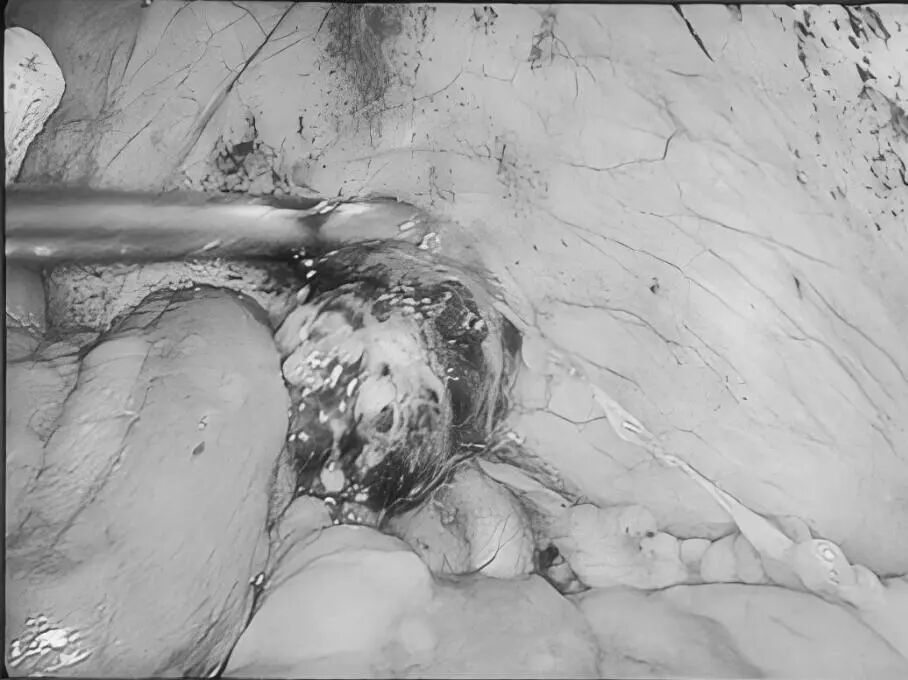

一名女性患者长期受到下腹部坠胀、排便不适等症状困扰,近期发现盆腔内存在肿物,严重影响其生活质量,为寻求进一步诊治,她前往贵州航天医院普外科就诊,经核磁共振(MRI)检查提示:盆腔内直肠与骶骨之间有一个“骶前囊肿”。由于该囊肿位置深,且与周围重要的神经和血管关系密切,若采用传统手术不仅创伤大,还伴随一定的风险。 面对这一棘手难题,普外科立即组织了麻醉科、医学影像科、妇科、重症医学科在内的多学科专家会诊(MDT)。经专家团队详细评估,与患者及家属充分沟通后,为患者制定并成功实施了“腹腔镜下骶前囊肿切除术”。术后恢复良好,不久便康复出院。 【疾病科普|什么是骶前囊肿?】 骶前囊肿,可以理解为生长在骨盆最深处、直肠后方的一个囊性肿物。由于它“躲藏”的位置非常特殊,四周紧邻着控制排便和感觉的重要神经与血管,因此被视为盆腔外科手术中的一个难点。 它可能带来哪些影响? 1.随着囊肿逐渐增大,可能会压迫直肠,引起排便困难或坠胀感。 2.压迫骶神经,可能导致腰骶部或会阴区的酸胀、疼痛。 3.囊肿本身也可能发生感染,形成脓肿,加重不适。 【技术介绍|腹腔镜下骶前囊肿切除术】 对于骶前囊肿这类较深的病灶,腹腔镜下骶前囊肿切除术提供了一种更为微创、便于操作的解决方案。 它是如何进行的? 医生仅通过腹部几个约0.5-1厘米的小孔,其中一个孔放入带高清摄像头的腹腔镜,将盆腔内的景象放大并清晰地投射到屏幕上,如同给了医生一双进入体内的“眼睛”。其他几个小孔则伸入细长的专用手术器械。医生看着屏幕,遥控这些器械,在清晰的视野下精细地分离并完整切除囊肿。 腹腔镜微创手术的特点包括: ▶创伤较小:避免了传统手术的长切口,体表疤痕小。 ▶视野清晰:放大后的图像让医生能更清楚地分辨囊肿与周围重要结构。 ▶操作精准:有助于更完整地切除囊肿,并尽力保护盆腔神经功能。 ▶恢复较快:因手术创伤小,患者术后疼痛感更轻,下床活动早,住院时间也可能缩短。 注:本文旨在进行健康科普,分享医疗案例与科普知识,不能替代任何专业的医疗建议。如有任何健康问题,请务必及时咨询并遵从专业医生的诊疗意见。 贵州航天医院普外科专家简介 高大勇 普外科(肛肠外科)学科带头人、名誉主任,主任医师、教授 临床擅长:对中西医结合诊治肛肠学科各种常见病、多发病及疑难杂症等具有丰富的临床经验。 原遵义市第一人民医院(遵义医科大学第三附属医院)、遵义市中医院肛肠科主任。中华中医药学会肛肠分会常委,全国中医肛肠学科名专家,中国健康促进与教育协会肛肠分会常委,中国康复医学会肛肠疾病康复专业委员会常委,中国民间中医医药研究开发协会肛肠分会副秘书长,中国医师协会中西医结合肛肠医师专业委员会常委,国家二级心理咨询师,贵州省第一批中医名医工作指导老师,遵义市名中医,遵义市肛肠学会会长,遵义市肛肠质控中心名誉主任,遵义市中西医结合学会名誉会长,遵义市健康科普专家,原贵州省中西医结合学会肛肠分会副主任委员、贵州省中医肛肠质控中心副主任、遵义市医学会医疗鉴定委员会专家、遵义市卫生系列高级评委。发表论文30余篇,主编和参编医学著作5本,主持省级科研课题2项、市级科研课题2项、院级科研课题1项。 梁 跃 普外科党支部书记、主任,主任医师 临床擅长:对普外科各类肿瘤手术具有丰富的临床经验。 毕业于遵义医学院,遵义市医学会小儿外科学分会常务委员,遵义市肛肠协会理事,遵义市医学会核医学分会(第二届)委员会委员;荣获第三期“黔医人才计划”优秀学员称号;主持市级课题1项,完成省级课题1项,在国内各类刊物上发表论文10余篇。 钱科洪 民盟盟员,普外科副主任医师 临床擅长:从事普外科临床工作30余年,对各类普外科疾病的诊治、乳腺、甲状腺、胃十二指肠、结直肠等疾病及疑难杂症具有丰富的临床经验。 毕业于遵义医学院临床医疗系,2009年前往中山大学附属第一医院微创外科进修学习,在国内各专业期刊发表论文数篇。 贵州航天医院普外科简介 基本情况 贵州航天医院普外科成立于1968年,前身属于原航天部O61基地3417医院外一科,1998年3417医院、3427医院合并后更名为普外科,下设胃肠外科、肛肠外科2个亚专业科室,拥有在全市较为先进的专科设备和技术,是中国疝病专科联盟单位,贵州医科大学附属医院胃肠外科专科联盟单位。开放床位40张,配备医护人员21人。 专科特色 普外科致力于胃肠及肛肠疾病的外科临床诊治及科研,以腹腔镜微创外科技术为本,形成以快速康复治疗胃肿瘤、结直肠肿瘤、小肠肿瘤、直肠脱垂、肥胖病、急腹症、各类疝、痔、瘘等专科特色,同时注重胃肠疾病尤其是结直肠恶性肿瘤的基础研究和临床转化研究,总体诊断和治疗水平在区域同级医院居于领先水平。 开展手术:腹腔镜下胃癌根治术,腹腔镜下袖状胃切除术,腹腔镜下胃肠道间质瘤切除术,腹腔镜下结、直肠癌根治术,胃癌、结直肠癌的精准治疗,腹腔镜下小儿疝气、成人疝修补术,腹腔镜下阑尾手术,内痔的硬化注射治疗及痔疮的微创治疗:ATH、PPH、TST,直肠脱垂的各种手术治疗,难治性伤口VSD技术,鼻胃肠管、肠梗阻导管置入术,肛肠术后间歇性导尿技术,并引进了中医适宜技术,也为各种化疗患者提供输液港安装,提高患者就医体验。 腹腔镜下腹股沟疝 无张力修补术 腹股沟疝里金斯坦 (Lichtenstein)手术 PPH微创术治疗环状混合痔 黏连性或炎性肠梗阻-肠梗阻导管 腹腔镜袖状胃切除 腹腔镜阑尾切除术 腹腔镜阑尾肿瘤切除术 腹腔镜下结肠癌根治术 诊疗范围 胃肿瘤、结直肠肿瘤、小肠肿瘤、肥胖症、各类急腹症、腹部外伤、腹壁疝、便秘、直肠脱垂、痔疮、肛瘘、肛裂等胃肠、肛肠外科疾病。 END